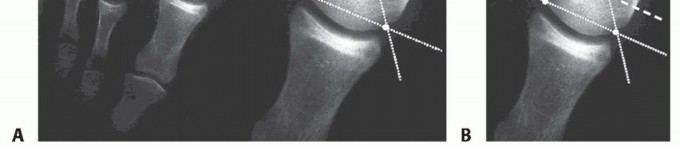

The DMAA is obtained by the intersection of the line that connects the articular edges of the head and the line bisecting the first metatarsal shaft. The DMAA normal value is up to 8 degrees (FIG 3).13,18 Inter- and intraobserver reliability for measuring the DMAA is poor.

FIG 3 • A. AP radiograph from a patient with juvenile hallux valgus in which the absolute congruence of the MTP joint can be noted. The misalignment of the distal articular surface of the metatarsal determines the hallux valgus deformity. B. Both edges of the metatarsal head articular surface are marked. The DMAA is measured between the line that connects the articular edges and the perpendicular to the diaphyseal axis of the first metatarsal. The normal value is up to 8 degrees.